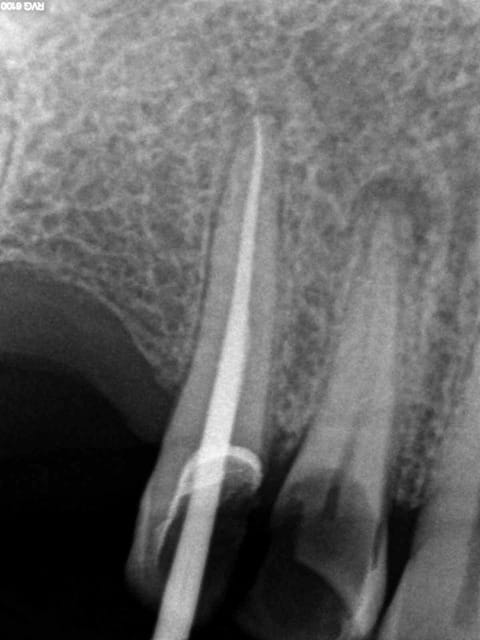

Aujourd'hui patient en urgence ca tombe bien pour une fois synchro avec un lapin.

45 mn de turbinage intensif 2 endos + 2 SC 33; On cote comment les radios ?

Z6, SC 20, Z3,Z3, SC20, Z3, Z3, SC 33, Z3, SC 33, Z3 ?